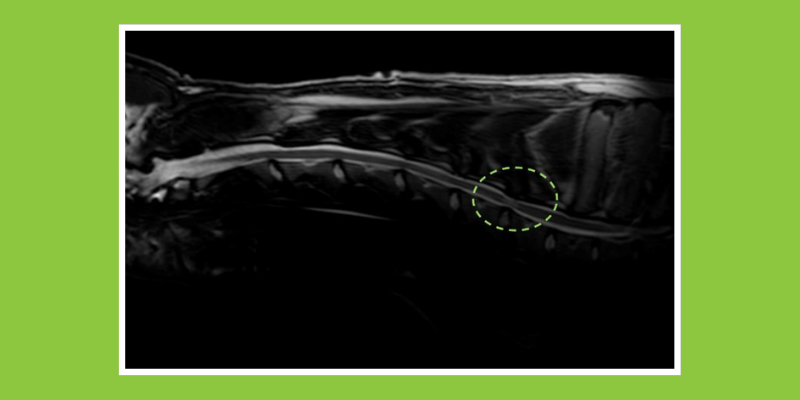

Wobbler disease is typically diagnosed with an MRI. This type of advanced imaging will show soft tissue structures, neural structures (spinal cord and nerves), and bones of the spine. MRI can help your veterinarian know the severity and extent of the disease, eliminate other possible causes of clinical signs, and determine treatment options.